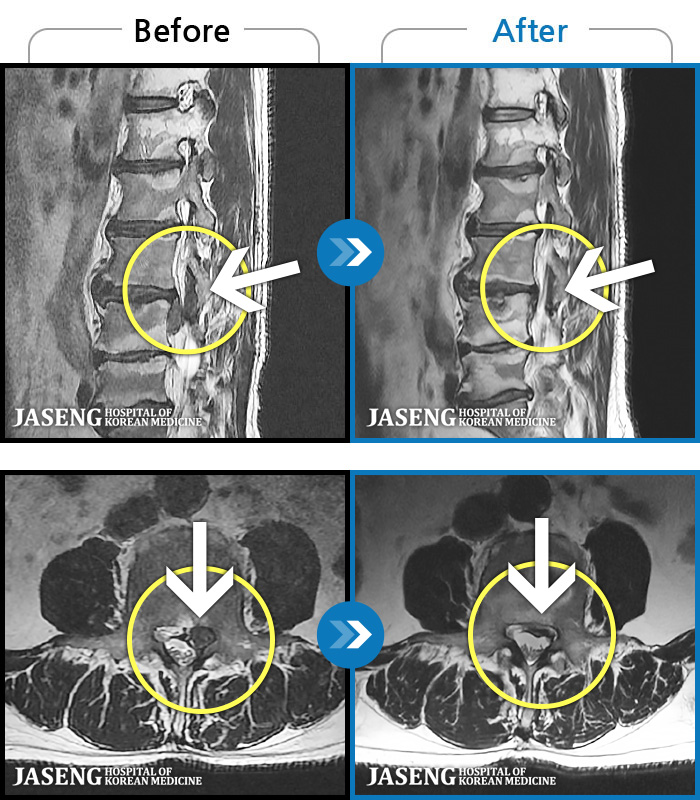

[] 03.04.01~09.11.01